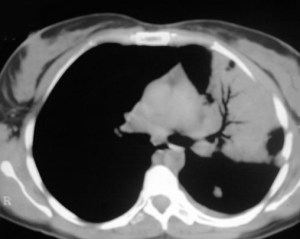

SIGNO DE LA INTERFASE

Este signo nos permite diferenciar entre derrame pleural y ascitis en un estudio de TC. Cuando existe una interfase nítida entre líquido y el hígado o el bazo, se trata de ascitis; cuando la interfase no es nítida, se trata de derrame pleural (flecha). El derrame pleural ocupa una posición más posterior y medial, mientras que la ascitis se localiza anterior y lateral al hígado y al bazo.